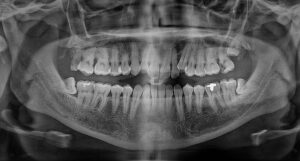

- Wisdom Teeth Extractions

- Guided Implant Surgeries